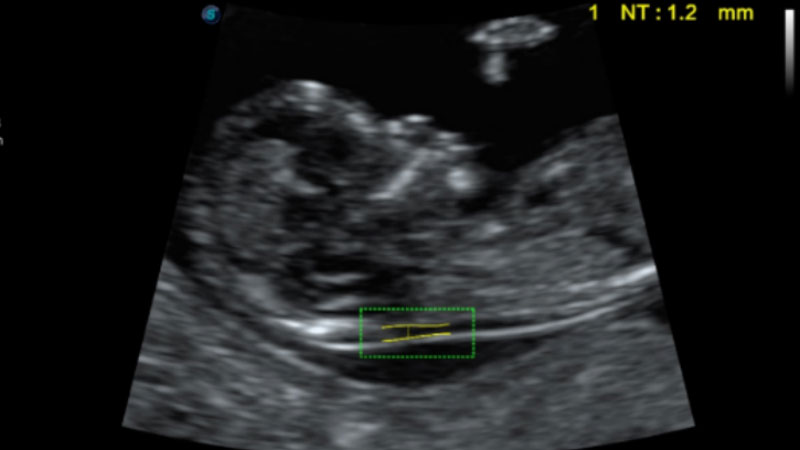

S-Fetus基于大數(shù)據(jù)深度學(xué)習(xí)算法,能夠幫助您在產(chǎn)前篩查過(guò)程中智能識(shí)別胎兒標(biāo)準(zhǔn)切面、自動(dòng)測(cè)量并錄入報(bào)告。一個(gè)按鍵,即可智能、精準(zhǔn)、高效地獲取胎兒生理指標(biāo),極大簡(jiǎn)化您的產(chǎn)科檢查操作。

可快速對(duì)產(chǎn)科掃查切面完成胎兒生理學(xué)參數(shù)的自動(dòng)測(cè)量,減少操作者按鍵次數(shù),大幅提升檢查效率。

自動(dòng)識(shí)別頸項(xiàng)透明層并獲得NT值,為早孕胎兒畸形篩查提供有效測(cè)量工具,提高診斷效率和診斷信心。